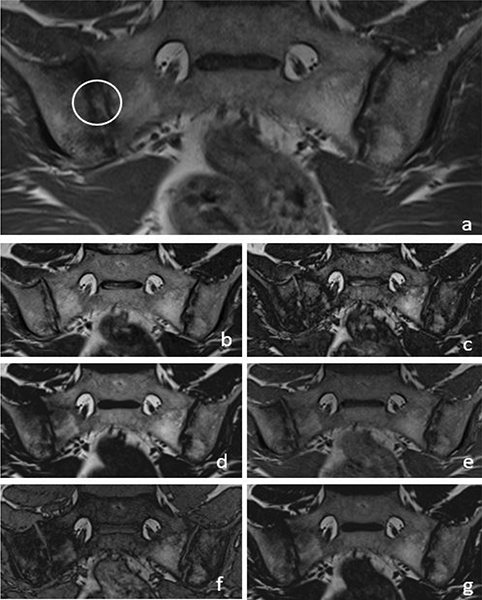

T1W–T2W Dixon FO, IP and OP images were found to be inadequate compared with those of the standard protocol for revealing the presence of subchondral sclerosis (Figure 2). T1W Dixon OP images were found to be insufficient to show backfill (P = 0.016), and other Dixon images were found to be similar to the standard protocol (Figure 4).

Figure 4

A 36‑year‑old male patient with backfill (circle) in the right sacroiliac joint on a T1W images (a). T2W Dixon IP (b), T2W Dixon OP (c), T2W Dixon FO (d), T1W Dixon IP (e), T1W Dixon OP (f) and T1W Dixon FO (g) images are also shown in the figure.